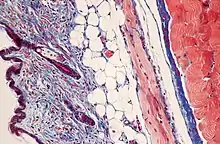

Masson's trichrome is a three-colour staining procedure used in histology. The recipes evolved from Claude L. Pierre Masson's (1880–1959) original formulation have different specific applications, but all are suited for distinguishing cells from surrounding connective tissue.

Most recipes produce red keratin and muscle fibers, blue or green collagen and bone, light red or pink cytoplasm, and dark brown to black cell nuclei.

Standard applications: Masson's trichrome staining is widely used to study muscular pathologies (muscular dystrophy), cardiac pathologies (infarct), hepatic pathologies (cirrhosis) or kidney pathologies (glomerular fibrosis). It can also be used to detect and analyze tumors on hepatic and kidney biopsies.[1]